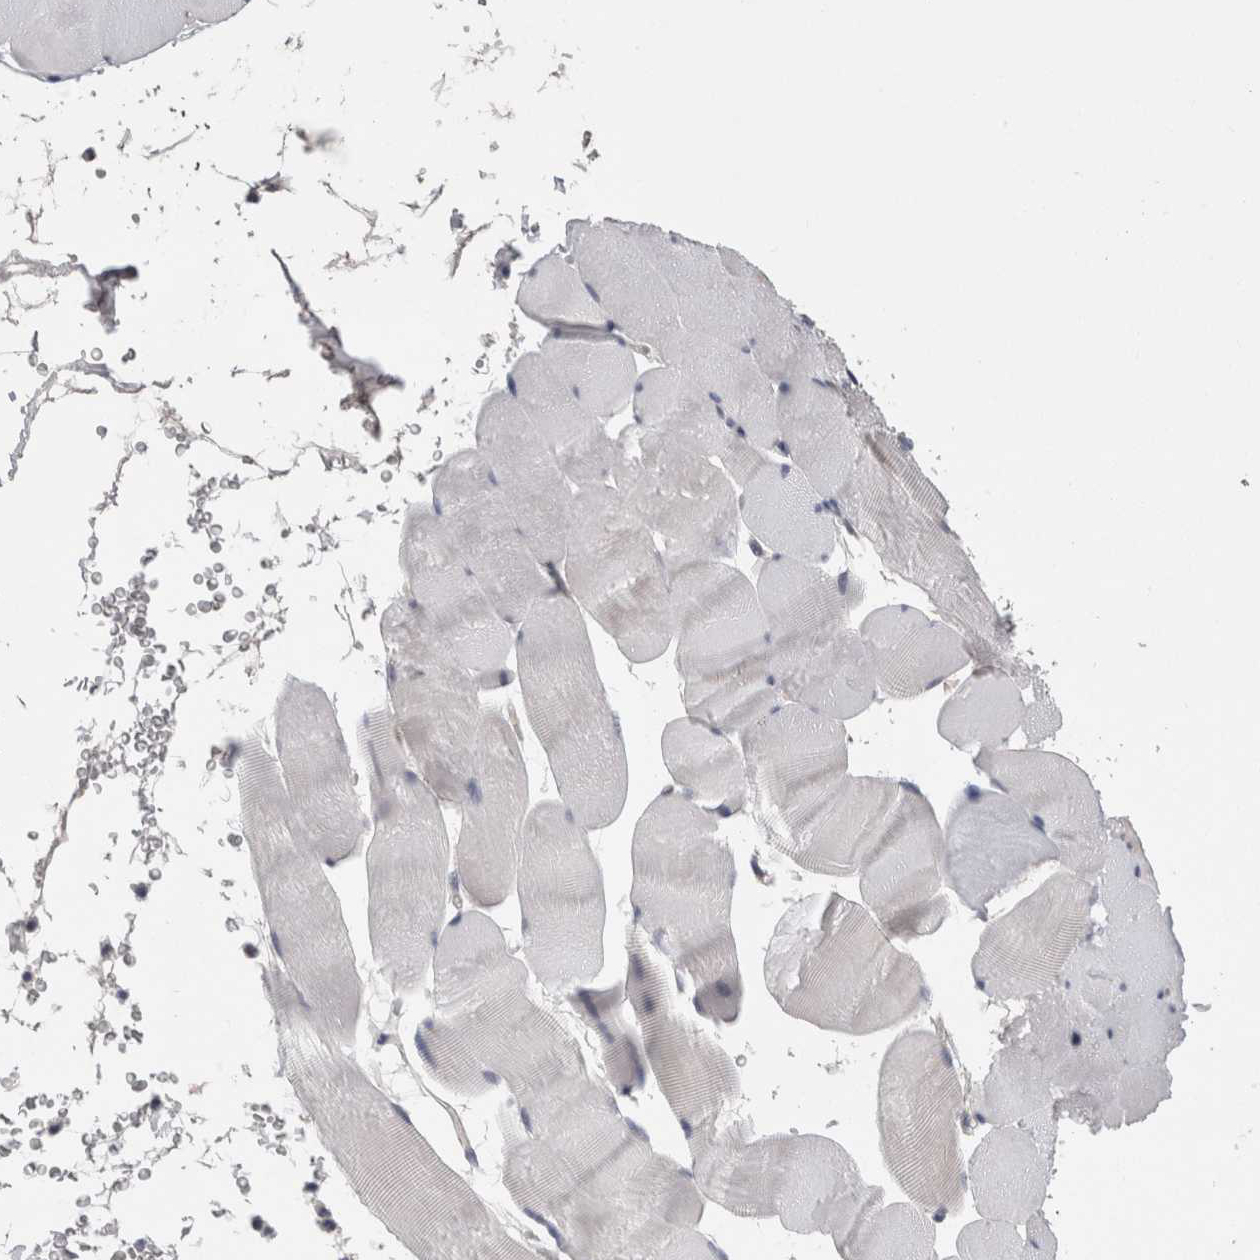

Immunohistochemical staining of human thyroid gland shows moderate cytoplasmic positivity in glandular cells.